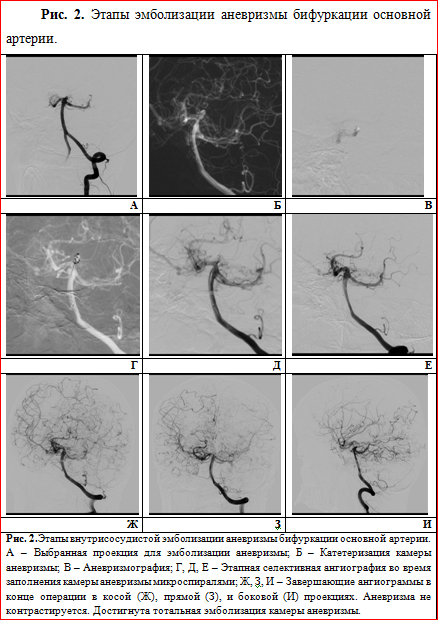

Под общим наркозом трансфеморальным доступом была катетеризирована камера аневризмы с последующей имплантацией в неё 3-х электролитически отделяемых микроспиралей. Манипуляция завершилась тотальной эмболизацией аневризмы с полным выключением её просвета из кровотока (тип А). Осложнений лечения отмечено не было, соматический и неврологический статус не пострадал (рис. 2).

В описанном нами случае имел место 3-й вариант паттерна ангиографической картины по Suzuki и Takaku с классическим расположением бифуркационных аневризм вертебробазилярного бассейна. В таких случаях внутрисосудистая эмболизация аневризмы на широкой ножке чаще всего предполагает применение дополнительных методик (таких как баллон- и/или стент-ассистенция), позволяющих избежать осложнений и повысить эффективность вмешательства, однако в нашем случае они не понадобились. В результате эмболизации было достигнуто полное выключение аневризмы из кровотока (типа А), что позволило минимизировать риск повторного кровоизлияния и значительно улучшить прогноз заболевания.